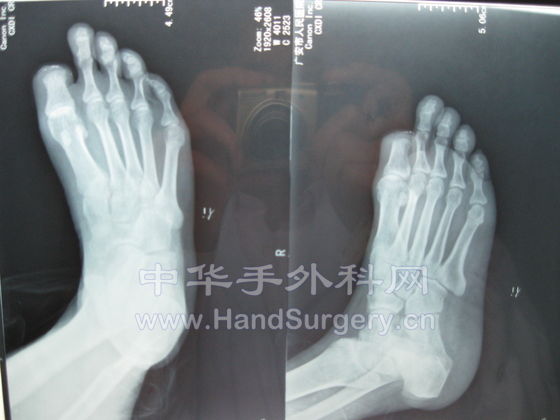

[其他] 动脉闭塞性脉管炎一例!~请前辈们指示!~

IMG_0115.jpg IMG_0116.jpg IMG_0117.jpg IMG_0118.jpg IMG_0119.jpg IMG_0120.jpg IMG_0121.jpg IMG_0122.jpg

患者于两年前无明原因出现右足麻木,疼痛,未经治疗!

于去年2008年12月份右足拇指甲沟炎,在外院行截指术后创面不愈合至今.

在外院以骨髓炎为诊断治疗至今.

下肢抬高(Buerger)试验阳性

足背动脉及胫后动脉未触及.